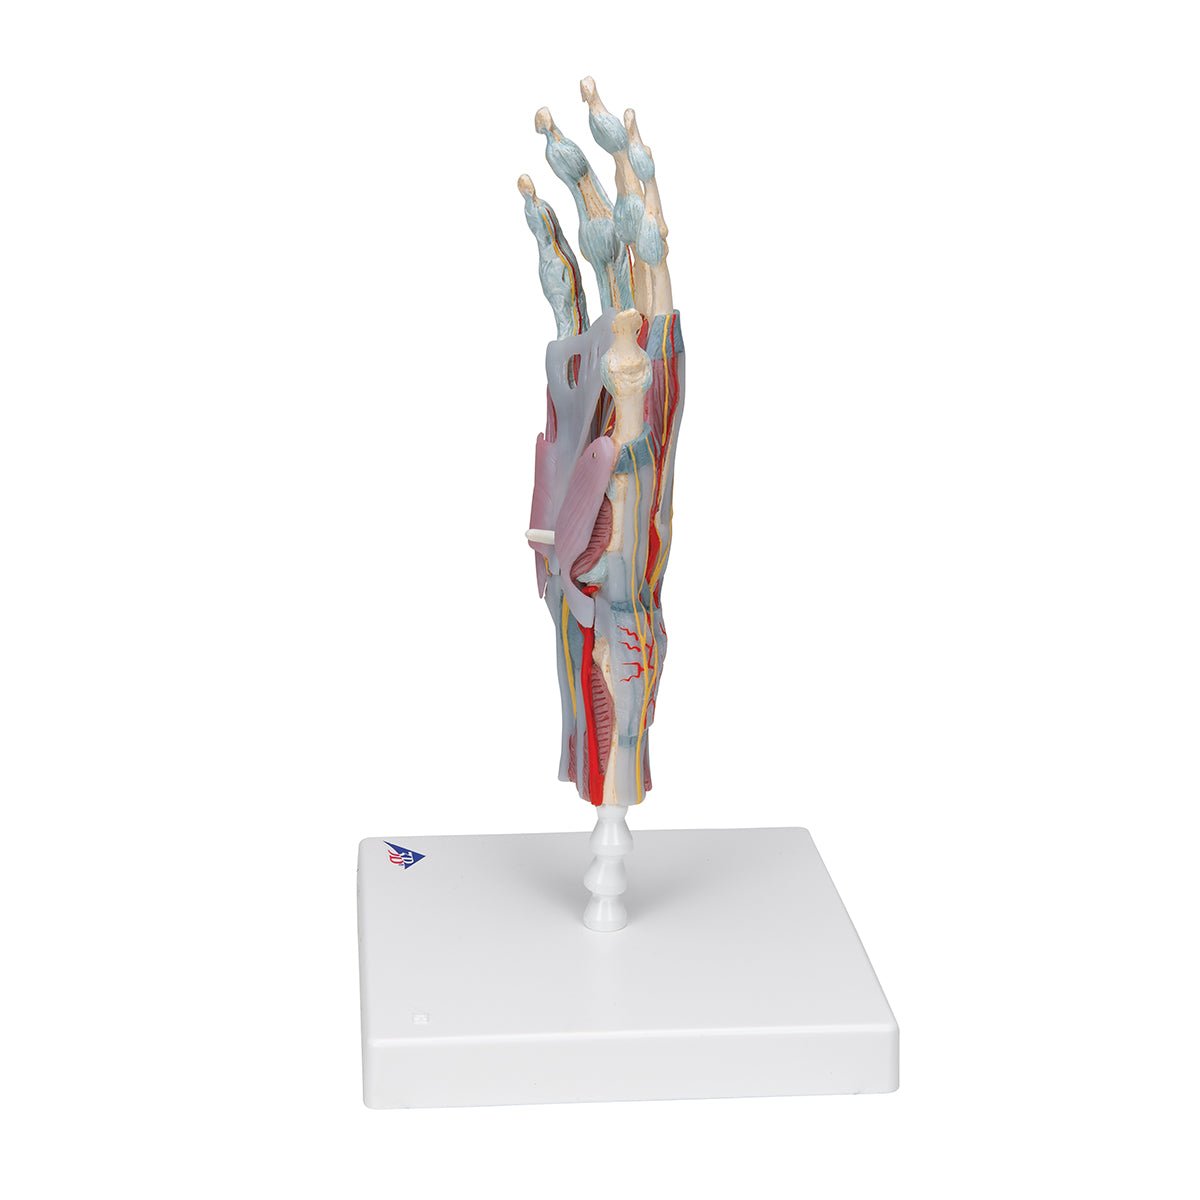

Salg af anatomiske modeller er det bærende element i eAnatomi, selvom vi også bruger mange ressourcer på at udvikle vores egne anatomiske materialer som fx plakater. Anatomiske modeller anvendes til forskellige formål og kan både vise afgrænset væv, organer samt organsystemer. Søger du en simpel model af knoglevæv eller måske en avanceret torso-model baseret på MRI teknologi, kan du finde det hele på eanatomi.com.